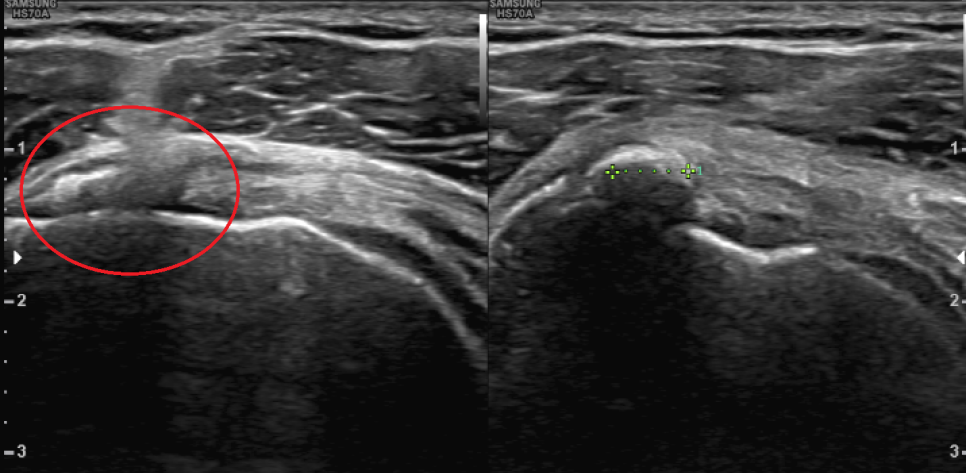

초음파 검사 후 발견된 돌덩이

엑스레이와 초음파 검사상 환자의 양 어깨 회전근개(극상근, 견갑하근)에 석회 덩어리가 관찰되어 어깨의 움직임에 많은 제한이 있는 상태에서 관찰되었습니다. 이러한 것들을 석회성 근염이라고 하며, 유착성 피막염이라고 진단을 받게 되었습니다.